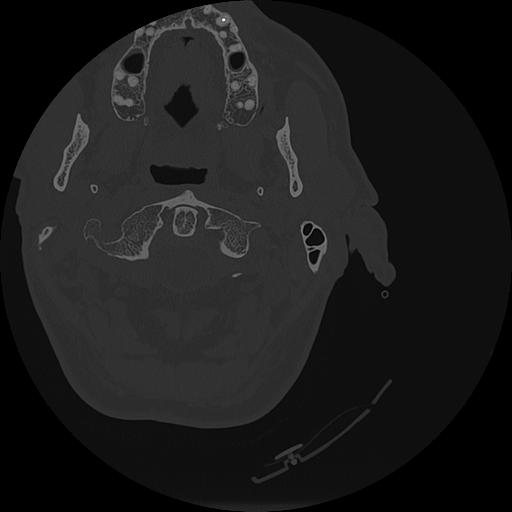

7 HUESO,,Vol,0.5,HUESO,,